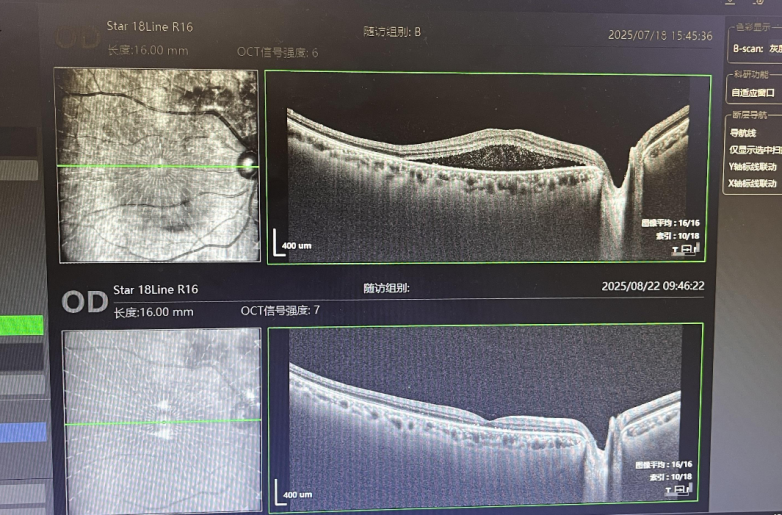

7月未打针与8月第一针后眼底照对比

在明确病情后,李志辉院长为梁伯制定了眼底注药治疗方案。梁伯先后在顺德爱尔眼科医院接受了3次眼底注药治疗。每次治疗后,梁伯都能明显感觉到右眼视力在逐步改善,从最初的0.12稳步提升至0.4,原本朦胧的世界变得越来越清晰。